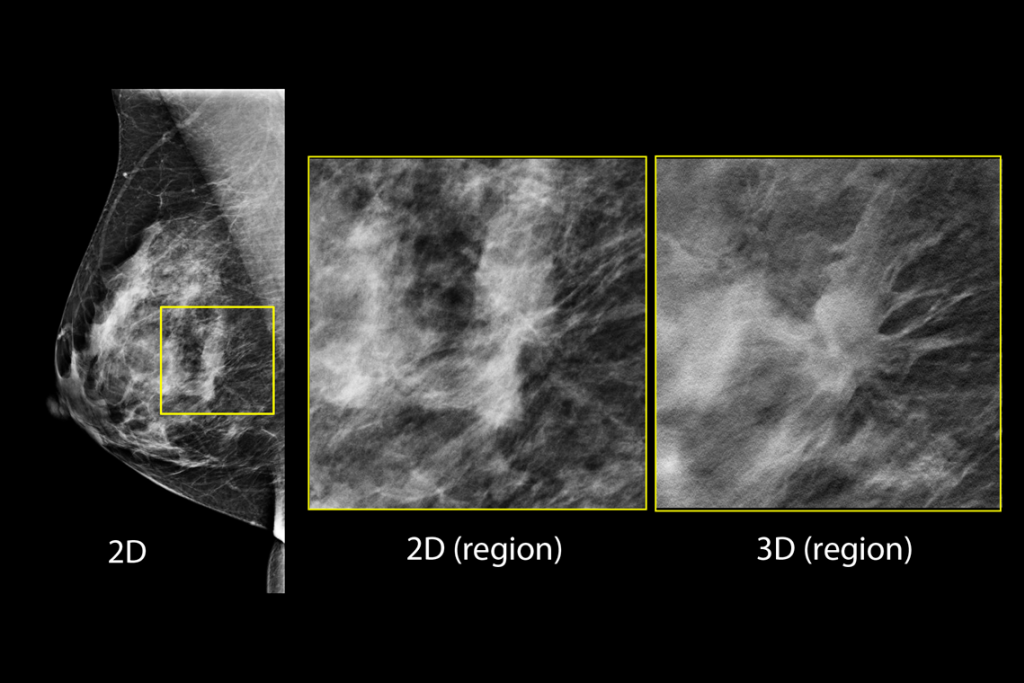

Klinische beelden van borstscan